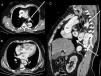

Varón de 57 años con antecedentes personales de hipertensión arterial y hernia de hiato que acude al Servicio de Urgencias por un cuadro de síncope y dolor torácico. Es diagnosticado de disección aórtica tipo A de Stanford, siendo sometido a cirugía urgente. Tras la intervención ingresa en la Unidad de Cuidados Intensivos. Para asegurar la nutrición enteral se intenta colocar una sonda nasogástrica con dificultades para su progresión, y se comprueba su posicionamiento con contraste, evidenciándose su malposicionamiento (fig. 1). Se revisa estudio de angio-TC torácico, observándose un hematoma aórtico secundario a la disección que produce compresión extrínseca del esófago con afilamiento progresivo y dilatación previa a la obstrucción (fig. 2). Finalmente requiere la colocación endoscópica para superar la estenosis esofágica.

TC toracoabdominal. A. Imagen axial preestenótica, donde se observa dilatación esofágica y disección aórtica. B. Imagen axial de la zona de compresión (asterisco blanco). C. Imagen coronal que demuestra afilamiento esofágico progresivo.

AI: aurícula izquierda; Ao: aorta con imagen de flap aórtico; AP: arteria pulmonar; VD: ventrículo derecho; VI: ventrículo izquierdo. Flecha blanca: dilatación esofágica pre y postestenosis. Asterisco blanco: zona de obstrucción esofágica.